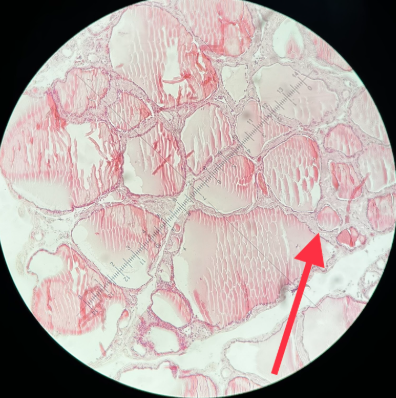

Kolloidne struuma ehk kolloidne hõõtsik